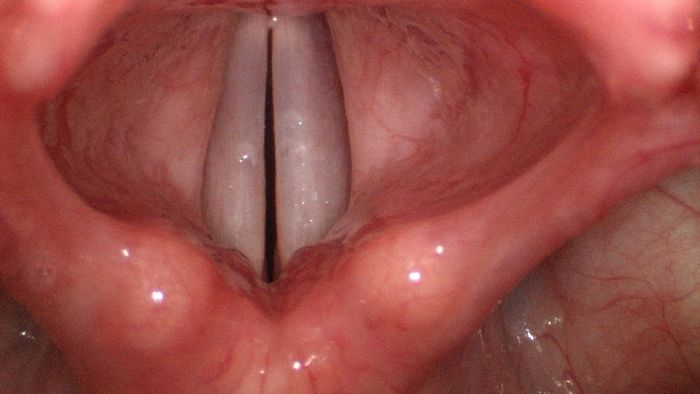

Vocal cords

but i have a dirty mind :D